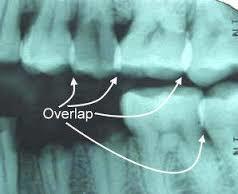

Radiografía Sobre expuesta Los interproximales no se pueden apreciar ya que el cono de la máquina no dirigió los rayos centralizados y cada pieza dental cubre a la adyacente.